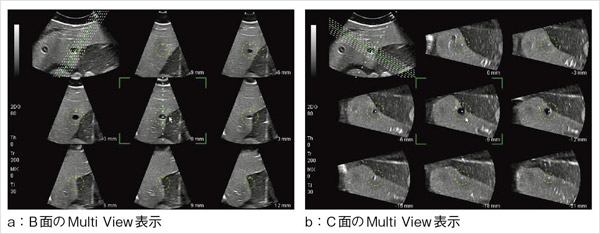

さらに,図7に示されるように,任意の半径の球面(ターゲットガイド)を表示することが可能で,腫瘍の広がりやRFAの焼灼範囲の目安として利用することができる。図8に,4D穿刺モードにおけるMulti View表示のファントム像を示す。B面のMulti View像(図8 a)は,穿刺経路に平行な断面の並列表示であり,C面のMulti View像(図8 b)は,穿刺経路の深さごとの断面の並列表示である。腫瘍の広がり,周囲臓器や周囲血管の位置,焼灼範囲の評価が容易である。図9は,RFA治療中の4D穿刺モード像である。ガイドラインに沿ってRFA針が刺入され,焼灼されている。ターゲットガイドの球面を目安に,焼灼状況を三次元的に観察することができる。

図8 4D穿刺モードにおけるファントムのMulti View表示